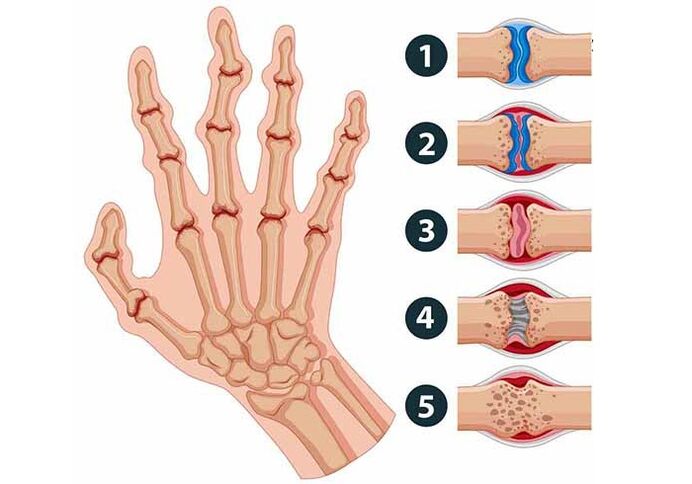

Fingergelenke können schmerzen, wenn folgende Pathologien vorliegen:

- Rheumatoide Arthritis. Diese Krankheit äußert sich in einer chronischen Form; Es betrifft kleine Gelenke, kann sich jedoch in einem sehr fortgeschrittenen Zustand auf große Gelenke sowie auf innere Organe ausbreiten. Sie schwellen an und werden rot und heiß. Das einfache Ballen der Faust ist nicht mehr so einfach wie zuvor, da die Beschwerden sehr stark sind. Oft sind beide Hände gleichzeitig betroffen. Die Besonderheit dieser Krankheit besteht darin, dass die Finger morgens und in den frühen Morgenstunden schmerzen.

- Psoriasis-Arthritis. Diese Art von Arthritis tritt ausschließlich an der Haut der Finger auf. Es kommt zu einer Schwellung, wodurch die Finger ihre Form verändern und wurstartig werden, rot mit einem leichten Blaustich.

- Infektiöse Arthritis. Diese Krankheit weist möglicherweise keine offensichtlichen Symptome auf. Wenn akute schmerzhafte Empfindungen auftreten, die zwischen einer Stunde und mehreren Tagen anhalten, bedeutet dies, dass sich die Krankheit bereits aktiv entwickelt. Das infizierte Gelenk ist warm und kann Fieber und Schüttelfrost verursachen.

- Gicht. Sehr häufig betrifft diese Krankheit Menschen über 50 Jahre. Die Krankheit entsteht aufgrund einer schlechten Ausscheidung von Harnsäure aus dem Körper; sammelt sich in den Gelenken an.

- Arthrose. Diese Krankheit beginnt, die Form der Gelenke zu verändern, sie werden dicker und schränken die Bewegung ein. Ältere Frauen sind anfälliger für diese Krankheit. Die Gründe für die Entstehung einer Arthrose: Vererbung, erhöhter Stress und viele andere Faktoren. Die Krankheitssymptome sind meist leicht erkennbar: Schmerzen, spindelförmige Verformung der Finger.